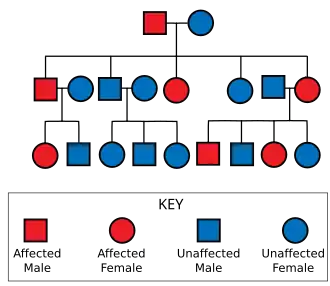

Inheritance

Huntington's disease has autosomal dominant inheritance, meaning that an affected individual typically inherits one copy of the gene with an expanded trinucleotide repeat (the mutant allele) from an affected parent.[29] Since the penetrance of the mutation is very high, those who have a mutated copy of the gene will have the disease. In this type of inheritance pattern, each offspring of an affected individual has a 50% risk of inheriting the mutant allele and developing the disease (see figure). This probability is sex-independent since the huntingtin gene is not located on the X or Y chromosomes.[40][41]

Trinucleotide CAG repeats numbering over 28 are unstable during replication, and this instability increases with the number of repeats present.[29] This usually leads to new expansions as generations pass (dynamic mutations) instead of reproducing an exact copy of the trinucleotide repeat.[29] This causes the number of repeats to change in successive generations, such that an unaffected parent with an "intermediate" number of repeats (28–35), or "reduced penetrance" (36–40), may pass on a copy of the gene with an increase in the number of repeats that produces fully penetrant HD.[29] The earlier age of onset and greater severity of disease in successive generations due to increases in the number of repeats is known as genetic anticipation.[1] Instability is greater in spermatogenesis than oogenesis;[29] maternally inherited alleles are usually of a similar repeat length, whereas paternally inherited ones have a higher chance of increasing in length.[29][42] Rarely is Huntington's disease caused by a new mutation, where neither parent has over 36 CAG repeats.[43]

In the rare situations where both parents have an expanded HD gene, the risk increases to 75%, and when either parent has two expanded copies, the risk is 100%. Individuals with both genes affected are rare. For some time, HD was thought to be the only disease for which possession of a second mutated gene did not affect symptoms and progression,[44] but it has since been found that it can affect the phenotype and the rate of progression.[29][45]

During the rediscovery of Mendelian inheritance at the turn of the 20th century, HD was used tentatively as an example of autosomal dominant inheritance.[121] English biologist William Bateson used the pedigrees of affected families to establish that HD had an autosomal dominant inheritance pattern.[128][123] The strong inheritance pattern prompted several researchers, including Smith Ely Jelliffe, to attempt to trace and connect family members of previous studies.[121] Jelliffe collected information from across New York and published several articles regarding the genealogy of HD in New England.[129] Jelliffe's research roused the interest of his college friend, Charles Davenport, who commissioned Elizabeth Muncey to produce the first field study on the East Coast of the United States of families with HD and to construct their pedigrees.[130] Davenport used this information to document the variable age of onset and range of symptoms of HD; he claimed that most cases of HD in the US could be traced back to a handful of individuals.[130] This research was further embellished in 1932 by P. R. Vessie, who popularized the idea that three brothers who left England in 1630 bound for Boston were the progenitors of HD in the US.[131] The claim that the earliest progenitors had been established and eugenic bias of Muncey's, Davenport's, and Vessie's work contributed to misunderstandings and prejudice about HD.[123] Muncey and Davenport also popularized the idea that in the past, some with HD may have been thought to be possessed by spirits or victims of witchcraft, and were sometimes shunned or exiled by society.[132][133] This idea has not been proven through scientific research. Researchers have found contrary evidence; for instance, the community of the family studied by George Huntington openly accommodated those who exhibited symptoms of HD.[123][132]